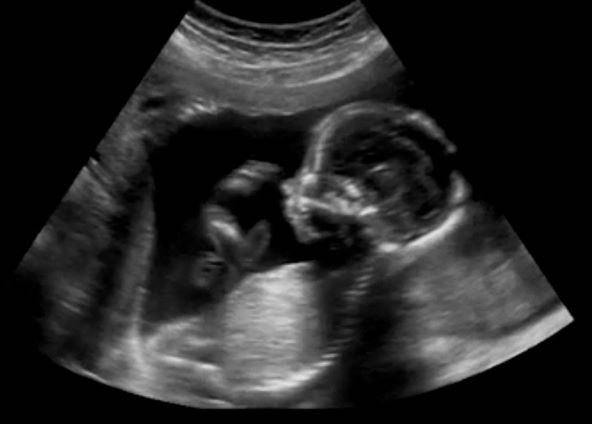

Ginekolog dr. Ankesh Sahetya na Instagramu je podijelio vrlo zanimljiv video s ultrazvuka na kojem se vidi izuzetno živahna beba, kako se prevrće i okreće, rita, "skače"...

"Bebini pokreti znak su da fetus raste i jača. Mame prve osjete te pokrete, a kasnije ih mogu osjetiti i drugi. Ženama se obično savjetuje da promatraju i budu svjesne kretnji bebe u trbuhu", napisao je uz ovaj šaljivi video, a komentari su se nizali.